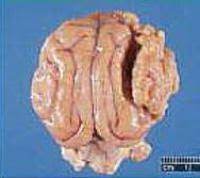

Any tumor that presses on other structures probably causes pain. The most common sign of a brain tumor in a dog is seizures. They come in three grades (1, 2, or 3). New masses may indicate an infection or abscess, a benign growth such as a fatty lipoma or cyst or a malignant tumor such as a mast cell tumor. These can lead to a fluid buildup which makes your dog feel as if they are constantly drowning. It is important to tell whether or not a dog tumor has spread internally. Brain tumours in dogs and cats can cause a wide variety of clinical signs which vary according to the part of the brain that is affected. This was the brain tumor. So let's take some time with this concept and mast cell tumors. The key to a tumor's symptoms really depends on its location, says theodore schwartz, md, a neurosurgeon with the weill cornell brain and spine center. This question is not only very frightening for a dog lover, but also has some real medical ramifications. Unfortunately cancer in dogs is relatively common, especially in dogs older than 10. The most common sign of a brain tumor is seizures, especially if these seizures come on for the first time after a dog has passed the age of five years old.

Brain Tumor Treatment For Dogs May Soon Be Used In Human Patients Vtx Virginia Tech from vtx.vt.edu Often the first sign to develop is seizures (fits). Some masses may represent enlarged lymph nodes. Binta is friendly and always want to curdle around you but the sad thing about this dog is that it has been suffering from a brain tumour three years ago. The nose can also start bleeding, your dog might develop noisy breathing, and regular sneezing may be a feature. Abdul cannot bear the more financial burden of the dog's treatment so, he gifted me the dying dog because he knows that, at least. And some cancers just plain hurt: Now the dog owner, mr. Drastic decline in their appetite or no interest in eating at all